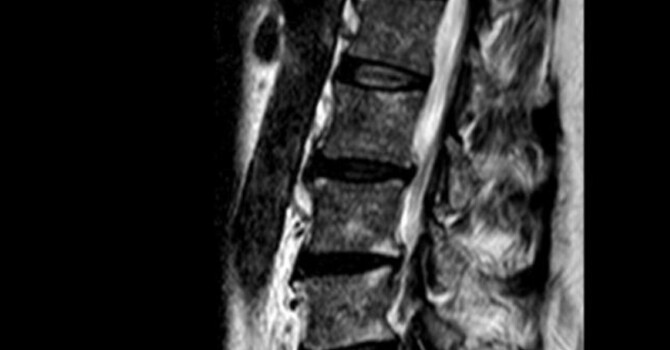

3. Disc Herniation

Slideshow image